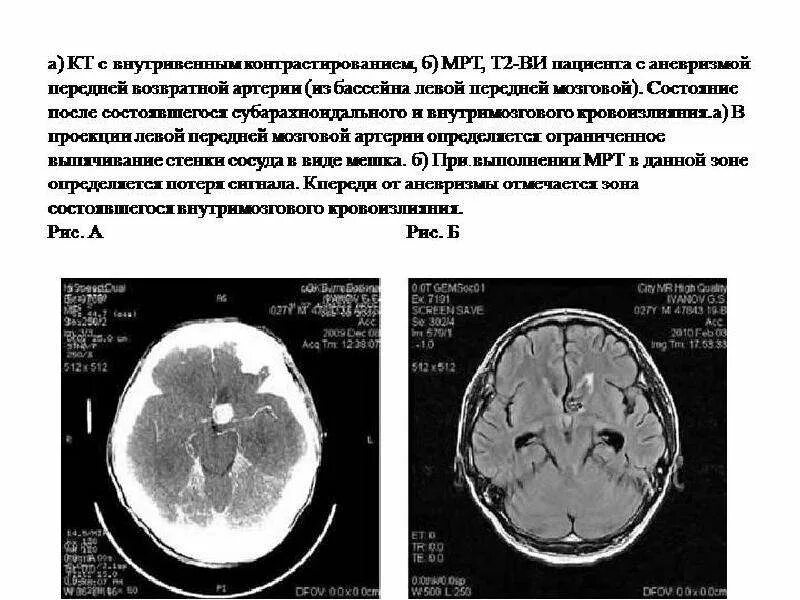

Аневризма головного мозга на кт